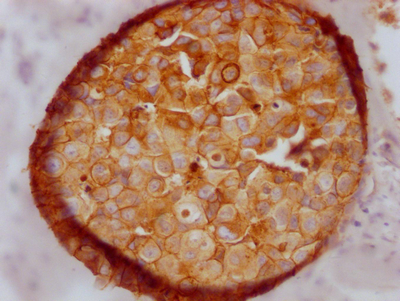

CDH1 Recombinant Monoclonal Antibody; CSB-RA005034MA1HU

CDH1 Recombinant Monoclonal Antibody

CSB-RA576116A0HU

CSB-RA005034MA2HU